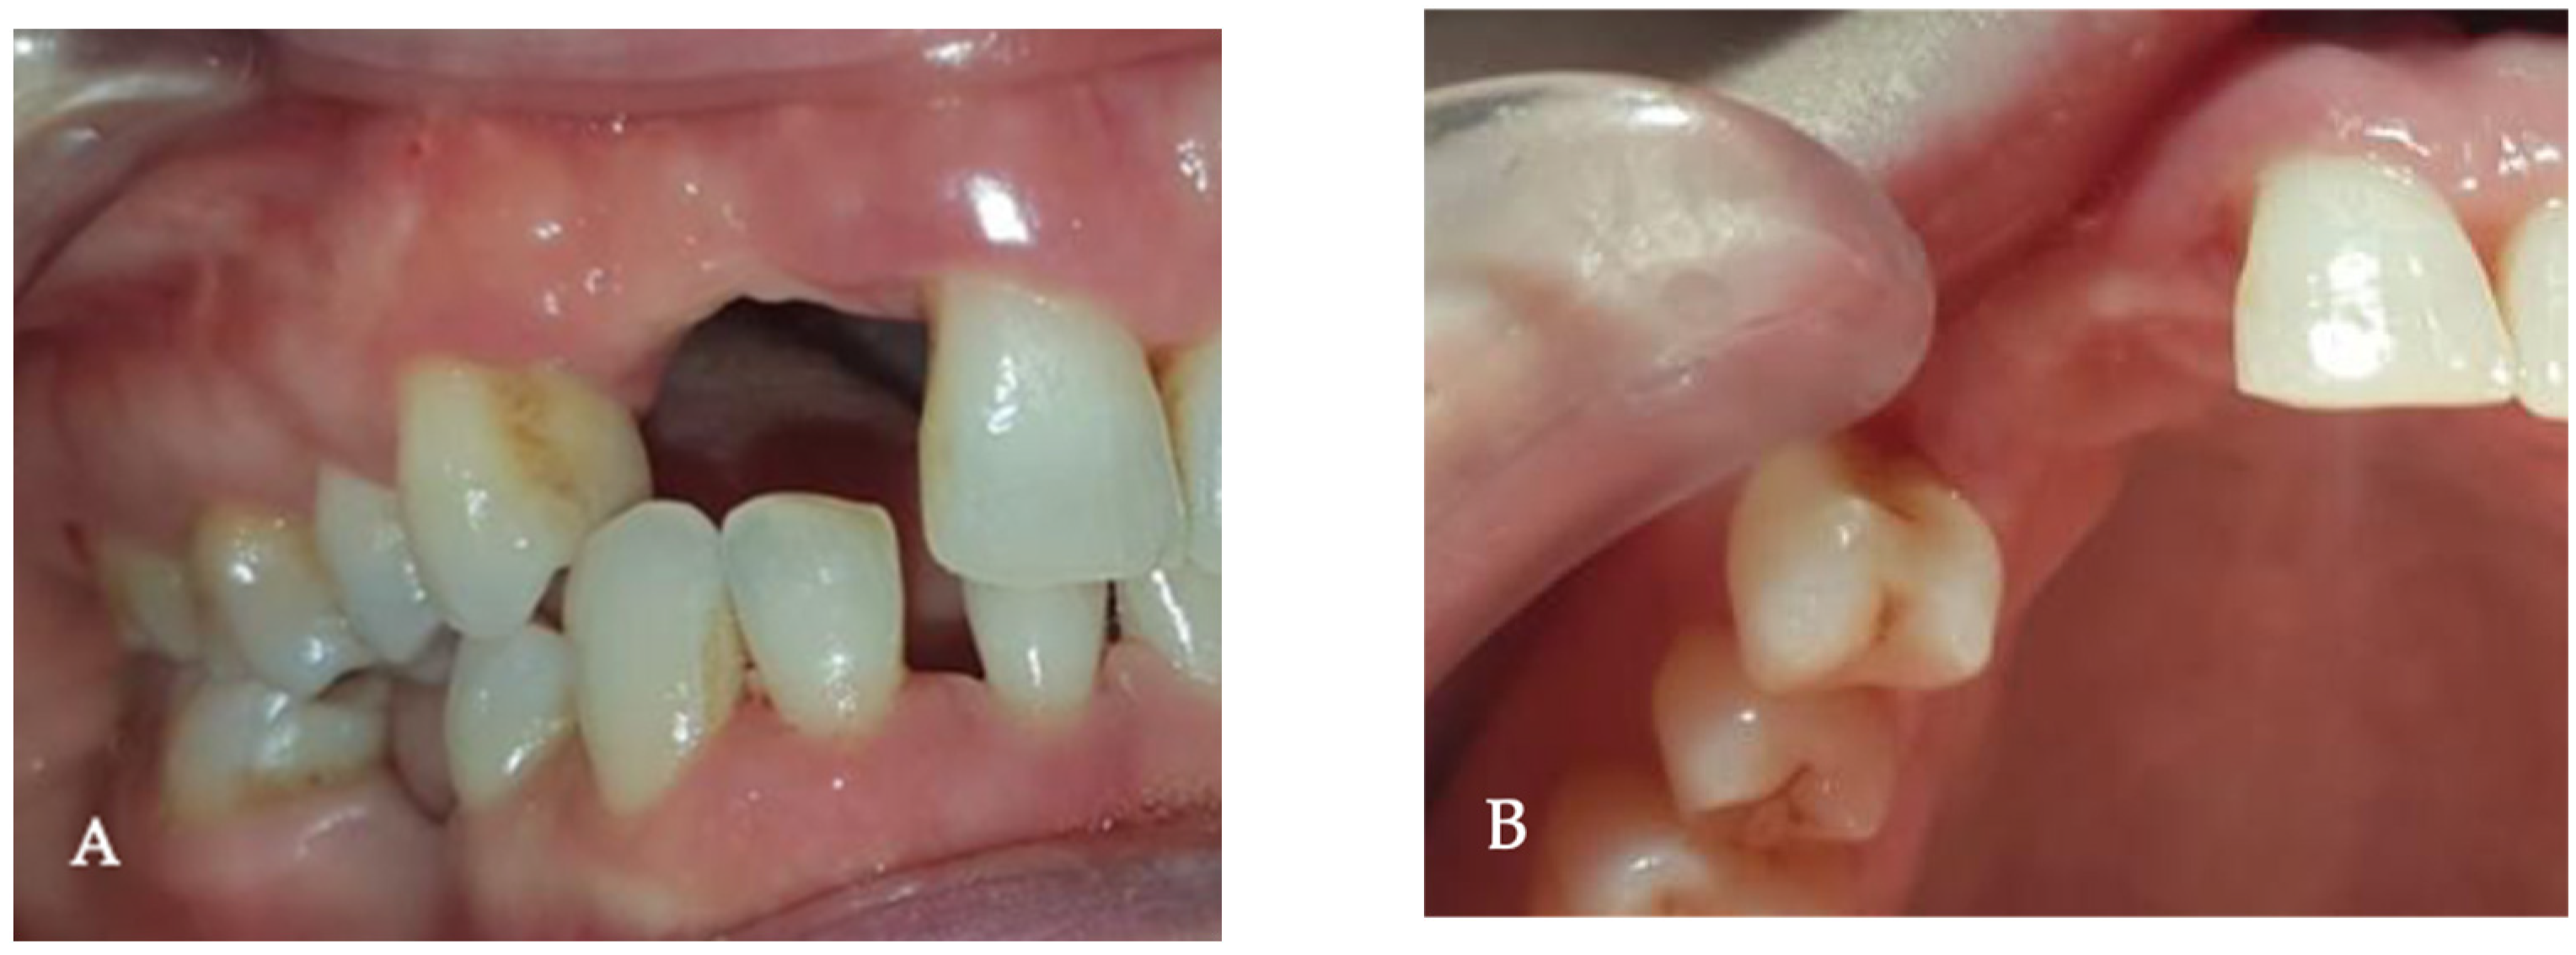

2. Case Presentation